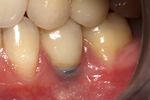

Peri-implantitis

Bone loss (peri-implantitis) on implants over 7 years in a heavy smoker

Cement peri-implantitis

Dental cement under the gingiva causes peri-implantitis and implant failure.